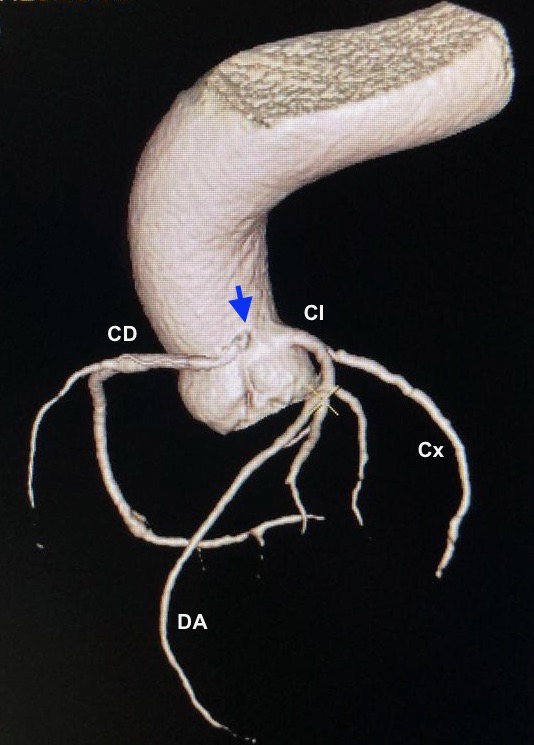

Presentamos el caso de un varón de 67 años de edad y múltiples factores de riesgo cardiovascular (dislipémico, diabético y exfumador), que acude a su cardiólogo del Hospital Vithas Pardo de Aravaca por dolor retroesternal al subir cuestas con sensación de taquicardia acompañante, que cedía con le reposo. La ergometría fue clínicamente positiva al presentar angina desde el minuto 2 de ejercicio. En el TAC de coronarias se objetivó el nacimiento anómalo superior de la coronaria derecha en el seno de Valsalva izquierdo, muy cerca a la unión con el seno derecho, existiendo un trayecto interarterial. Además, tanto la descendente anterior como la circunfleja presentaban placas no significativas del 30% y 40%, respectivamente.